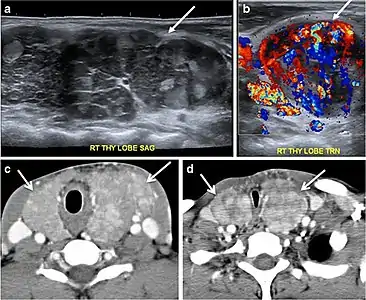

Thyroid nodules that are detected by an imaging study but have not been previously detected or suspected clinically are considered to be ITNs. ITNs are one of the most common incidental findings on neck imaging. ITNs are reported in up to 25% of chest CT scans, and in 16–18 % of cervical region cross-sectional imaging, including CT and MRI scans. The rate of malignancy in the detected ITNs on CT and MRI scans varies from 0% to 11%. Incidentally detected thyroid carcinomas are more likely to be papillary thyroid carcinomas (PTCs) (Fig. 3). Incidentally detected cancers tend to be smaller in size and less likely to have distant metastasis, as compared to clinically suspected thyroid cancers.[1]

Fig. 3. An incidental PTC in a 62-year-old male patient with lymphoma. a, b Enhanced axial CT scan and fused PET/CT scan of the neck demonstrate a well-defined, hypodense right thyroid nodule (white arrow) with high FDG uptake. The FDG-avid uptake in the left side (circle) is related to patient's known lymphoma, which resolved after treatment. c, d Transverse greyscale and sagittal colour Doppler ultrasound of the neck demonstrate a right thyroid irregular hypoechoic lesion with some micro-calcifications (white arrows) and increased vascularity.[1]

On CT scans, a malignant lesion is suspected when the margins are ill-defined and there is extra-thyroid extension, lymph node involvement, or invasion of the surrounding structures. The absence of these features does not exclude malignant tumours, especially papillary, follicular, and medullary thyroid carcinomas (Fig. 3). Therefore, ultrasound is the modality of choice for thyroid lesion evaluation, due to its superior spatial resolution compared to CT examinations. Sonographic features of malignancy are micro-calcifications, acoustic shadowing, anti-parallel orientation, marked hypoechogenicity, irregular or microlobulated margins, and increased vascularity. CT scans lack the ability to detect these reliable sonographic signs of malignancy. Therefore, further management of ITNs, if required, usually begins with thyroid ultrasound and FNA should be considered according to the ultrasound findings.[1]